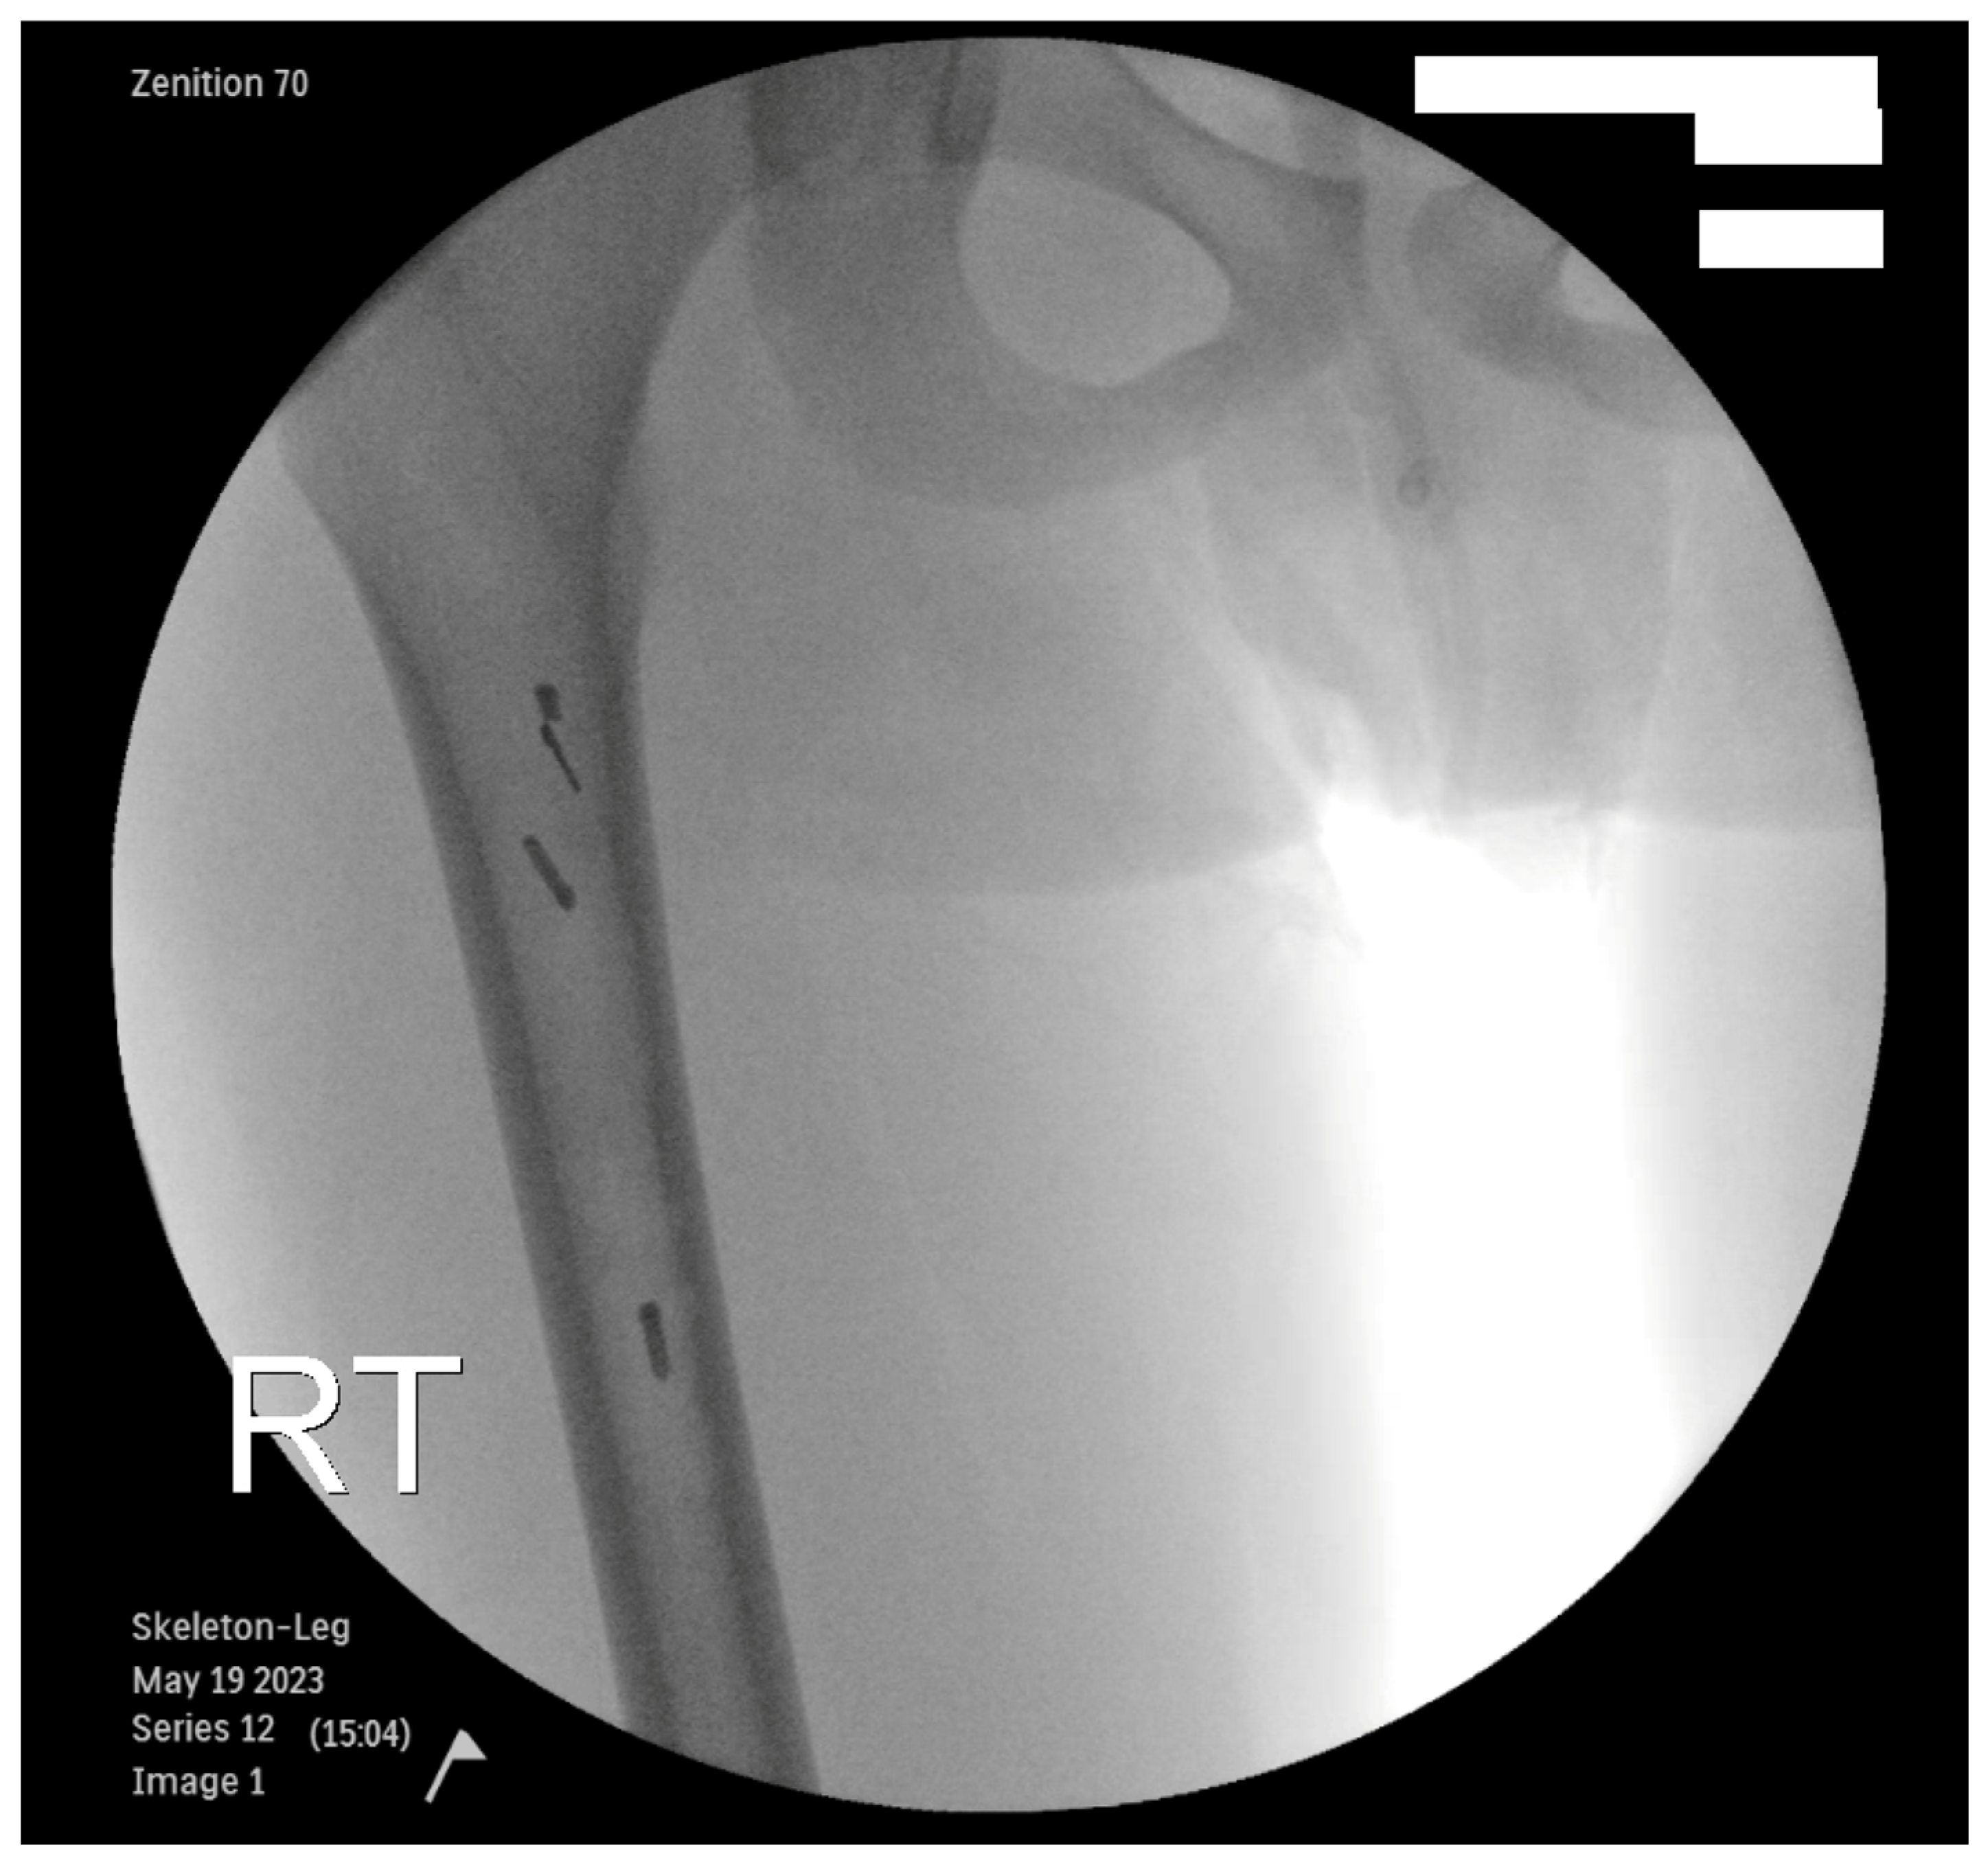

| 3 | Anterior cortical breach | Intraop | Fluoroscopy | Grade I | Nothing | No long-term sequelae | 670 days | No | None |